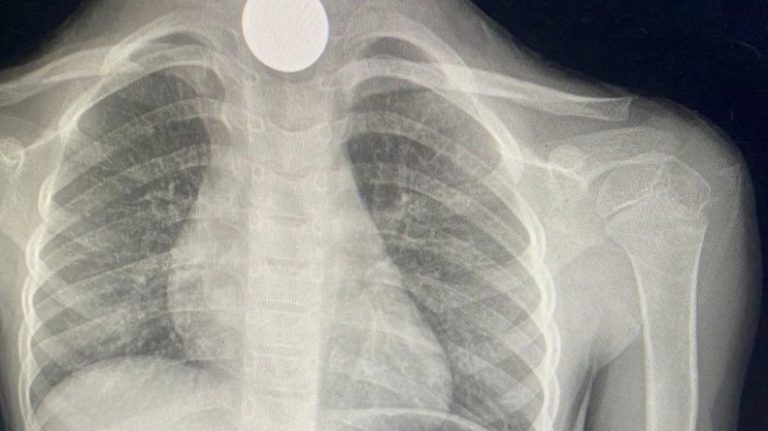

وأضافت “صحة الجوف” في تغريدة على “تويتر”، أن فريقًا طبياً في مستشفى طبرجل العام تمكن من إنقاذ حياة طفلة ٥ سنوات انقطع عنها الأوكسجين وكانت تعاني من مشاكل في التنفس نتيجة ابتلاعها قطعتين معدنتين.

وأشارت صحة الجوف، إلى أنه تم استخراج القطعتين المعدنيتين بعد وصولها لقسم الطوارئ، وخرجت بحالة جيدة.